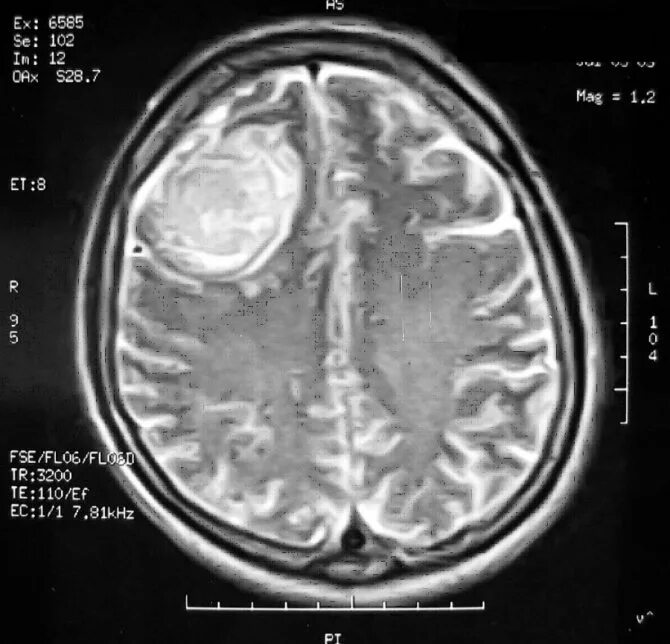

Отек головного мозга мрт